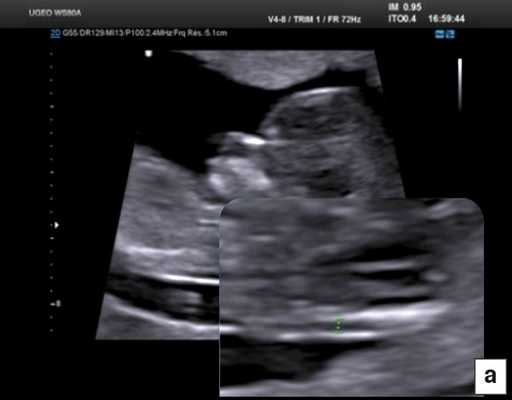

В начале 90-х годов прошлого века в практику был внедрен метод измерения толщины воротникового пространства (ТВП) в I триместре беременности, и к настоящему времени его считают показателем не только анеуплоидии, но и широкого спектра наследственных синдромов и пороков развития [2]. K. Николаидес (K. Nicolaides) с группой исследователей предложили новую модель скрининга на анеуплоидию и установили правила использования этого метода, в частности необходимость применения кривой обучения, проведения аудита, качественного (процедура оценки качества изображений) и количественного (медиана, дельты-ТВП и т.д.). Фонд медицины плода (Fetal Medicine Foundation) стандартизировал предложенный ими клинический протокол и установил правила сертификации для повышения качества медицинской помощи и уменьшения изменчивости результатов данных скрининга [3, 4]. Измерение ТВП можно проводить вручную (рис. 2a) или полуавтоматически (рис. 2b), чтобы результаты измерений были более воспроизводимыми. Кроме того, компания Samsung разработала дополнительный метод измерения показателей ТВП - 5D NT, позволяющий точно выявить срединно-сагиттальную плоскость и улучшить оценки по шкале Германа (Herman score).

Рис. 4. Диагностика хориальности и количества амнионов в I триместре путем оценки лямбда-признака (a) и T-признака (b).